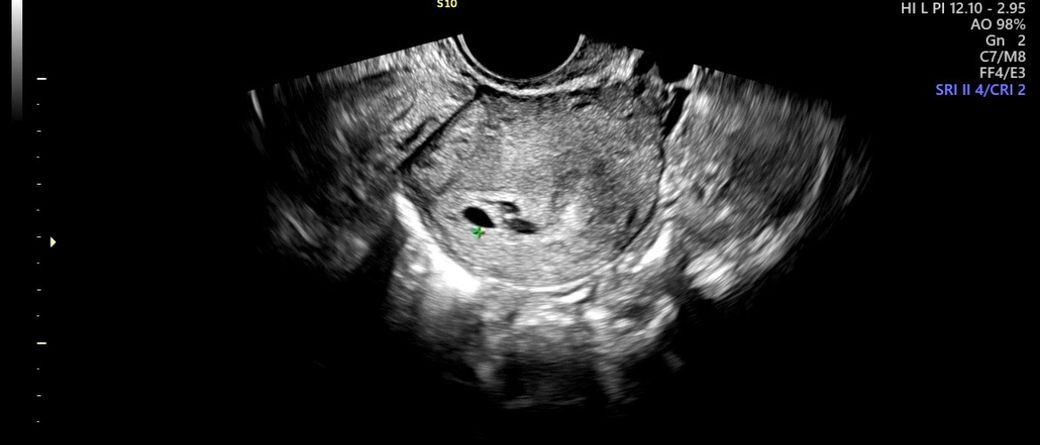

왼쪽에 있는게 아기집(0.54cm) 설명들었는데

그 옆쪽에 있는 두개 보이는건 뭘까요 ?? ㅠㅠ 피고임일까요? 걱정됩니다 ㅠㅠㅠ 위험한 건지 유산기 있는건지도 알려주세요 ㅠ